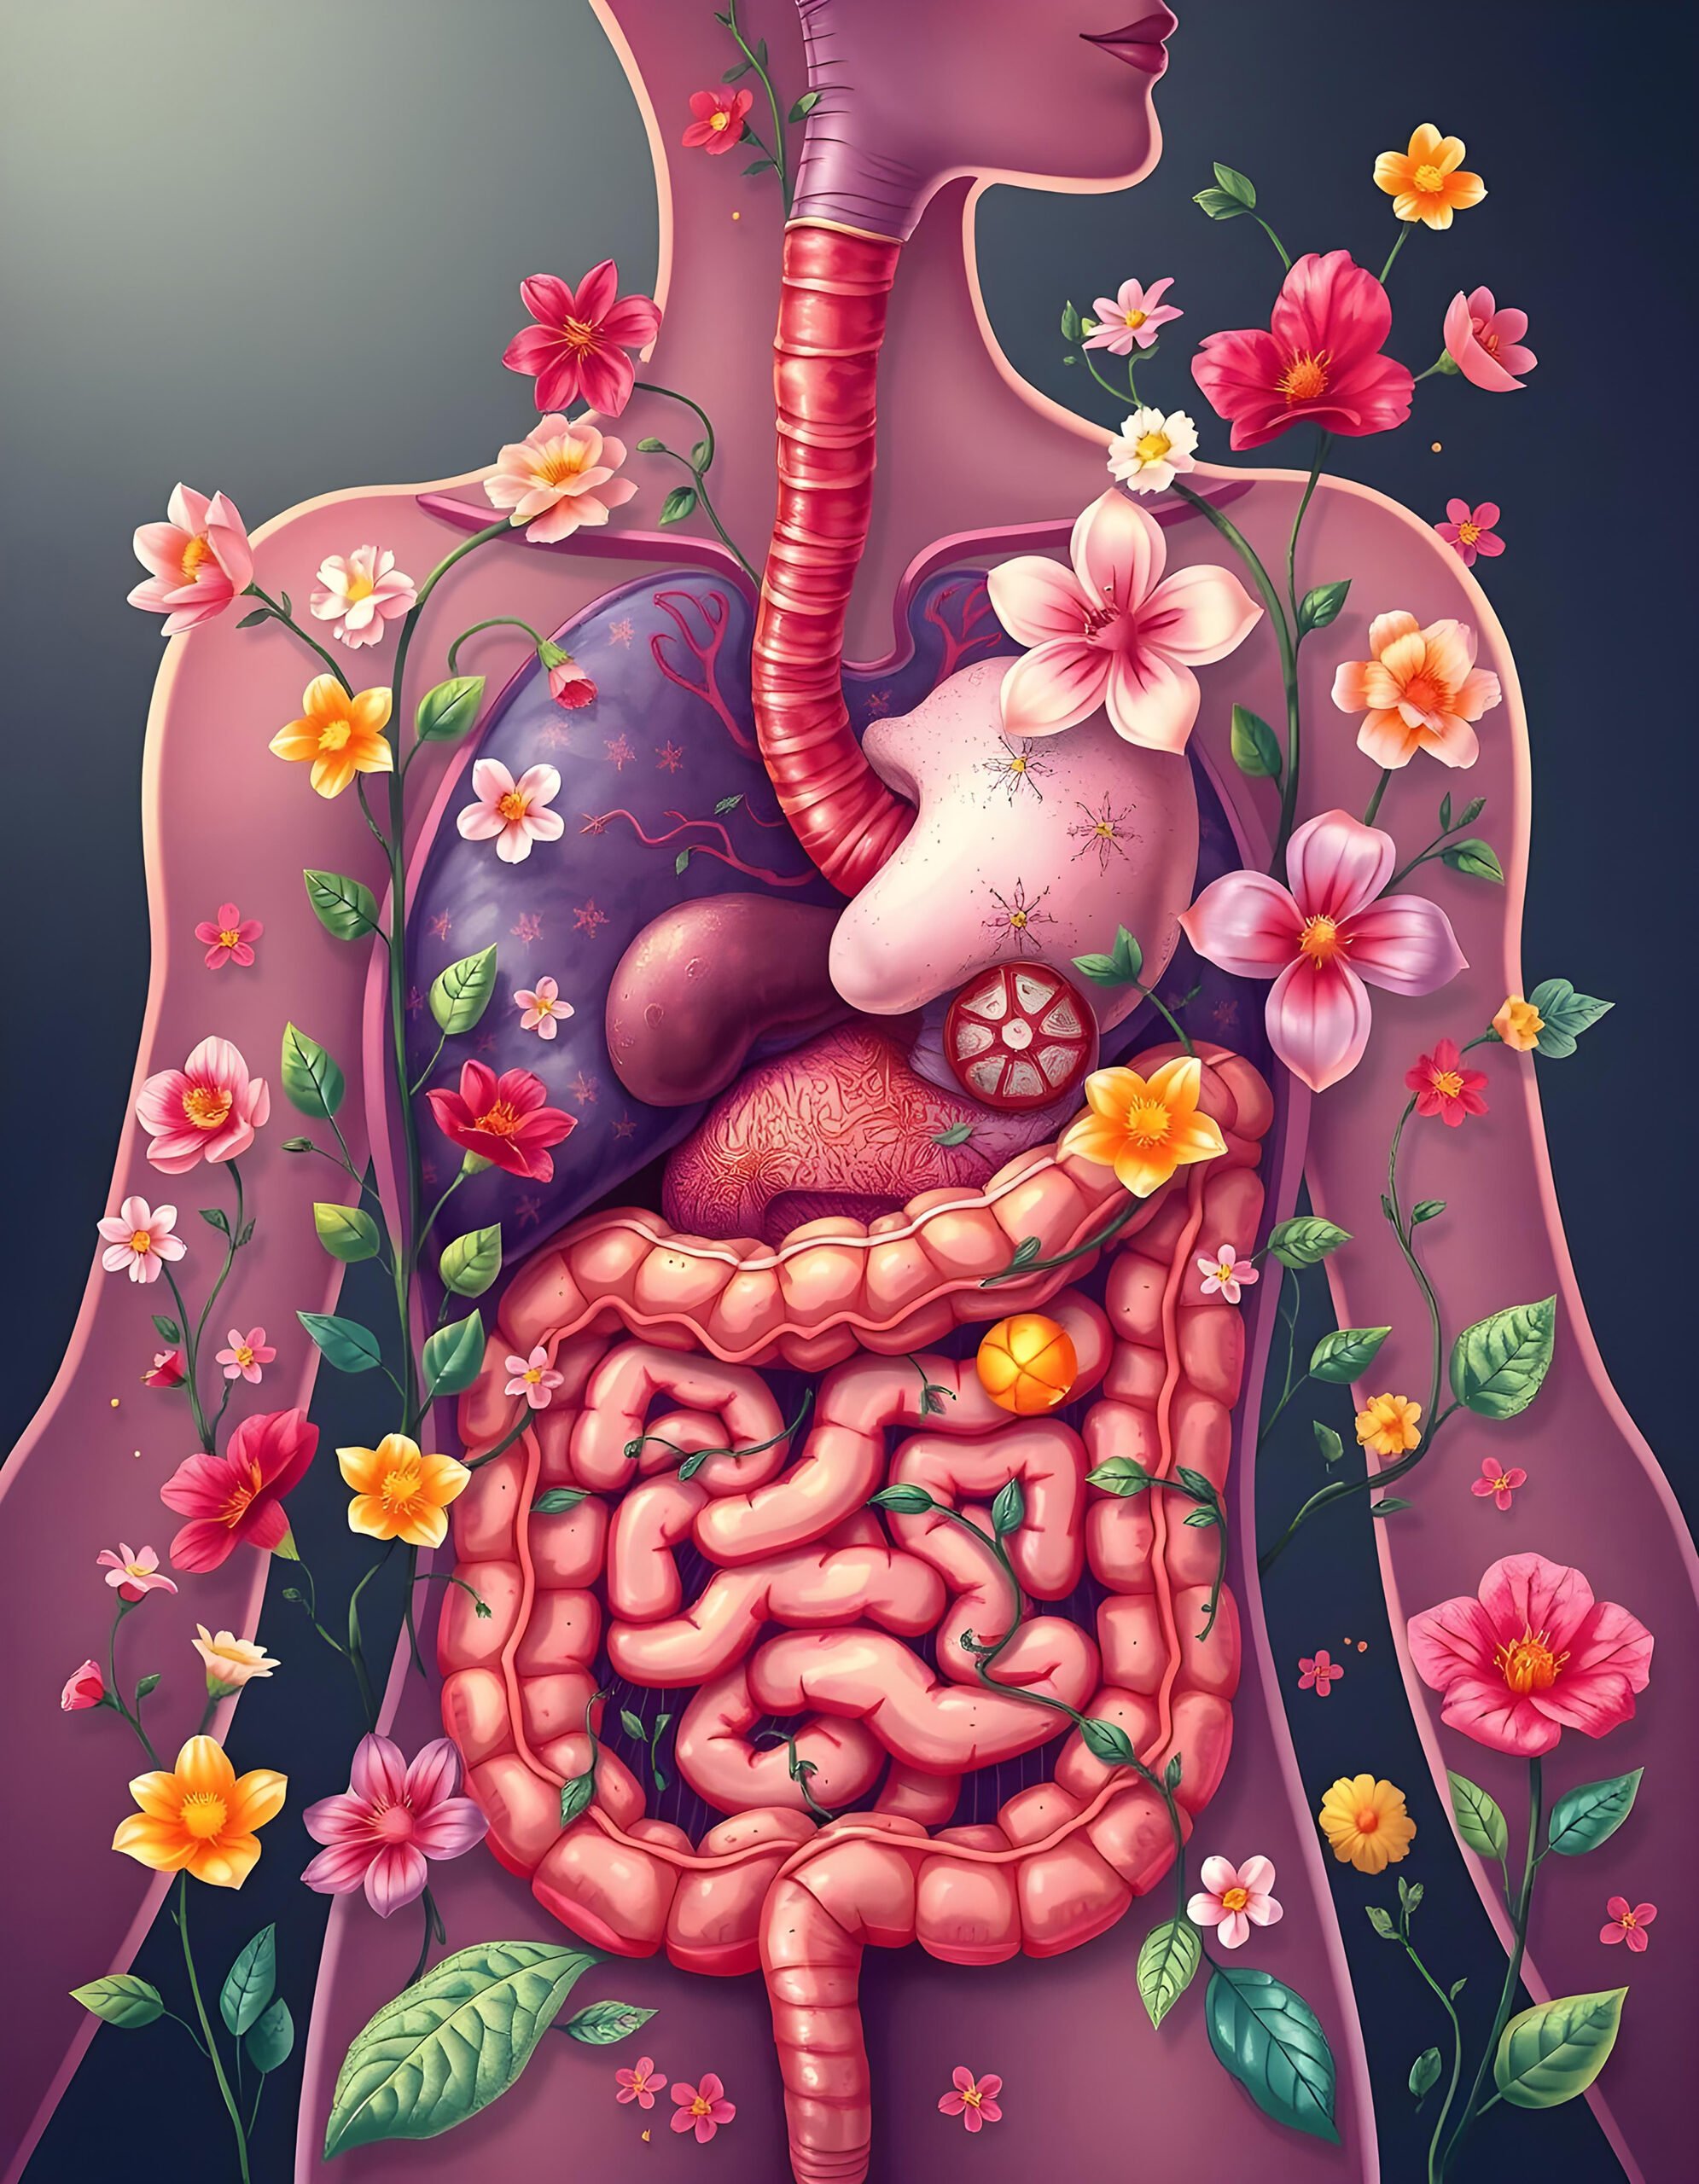

Dispepsia – Simptome comune și tratamentul pentru o digestie sănătoasă

Dispepsia, cunoscută și sub numele de indigestie, este o problemă digestivă frecventă. Aceasta, afectează milioane de persoane la nivel global. Deși termenul “dispepsie” poate suna tehnic și abstract, simptomele sale sunt extrem de reale și pot influența semnificativ calitatea vieții individului. Persoanele care se confruntă cu dispepsie pot experimenta disconfort abdominal, durere, balonare, greață și …